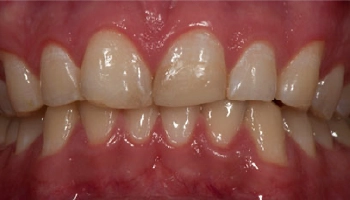

Reconstructive Dentistry: Implants & crowns

Before and after images of dental implants and crowns. Before and after comparison of dental implants and crowns.

Before and after reconstructive dentistry with dental implants and crowns. Before and after comparison of dental implants and crowns.